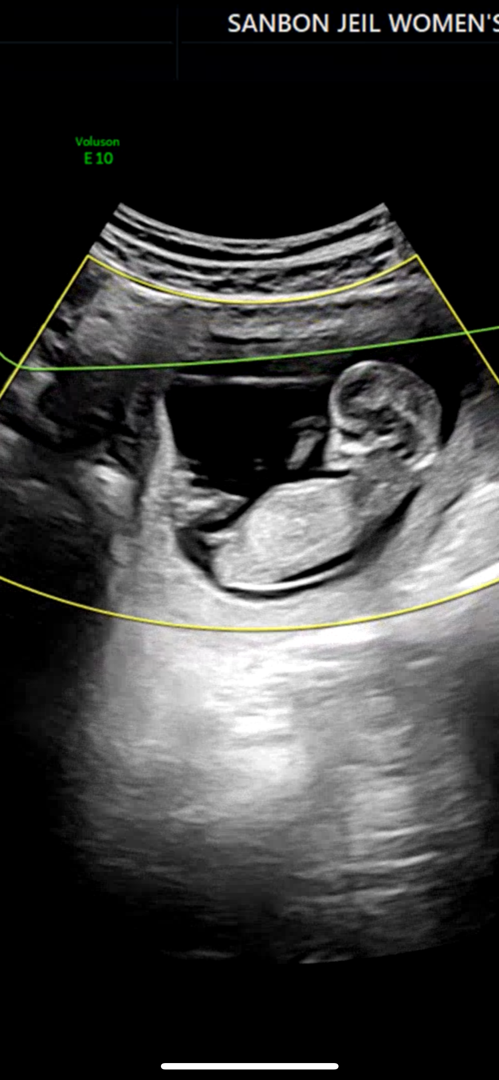

12주 각도법 성별

12주 기형아검사 하면서 촬영한 거예요~ 각도법 고수님들 확인 가능하실까요?! 🥺

저는 아들이요!

저는 남아같아요!

아들같아욤